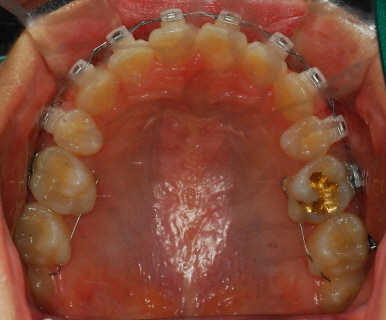

<상악 사진>

아아 쨋든 이번달 과정은 고무줄이구요 한가지 더~ 윗니가 예전사진을 보면 앞니 뒤가 많이 울퉁불퉁 한 것을 볼 수 있는데요 윗니와 아랫니가 서로 좀 더 가깝게 하기 위해 뒷부분을 좀 깎는 작업을 했습니다 치과쌤의 표현 방식을 빌리면 일종의 배가 나온 부분을 다이어트 시켰다고나 할까요?!ㅎㅎㅎㅎ (내 배도좀 해야될듯....)